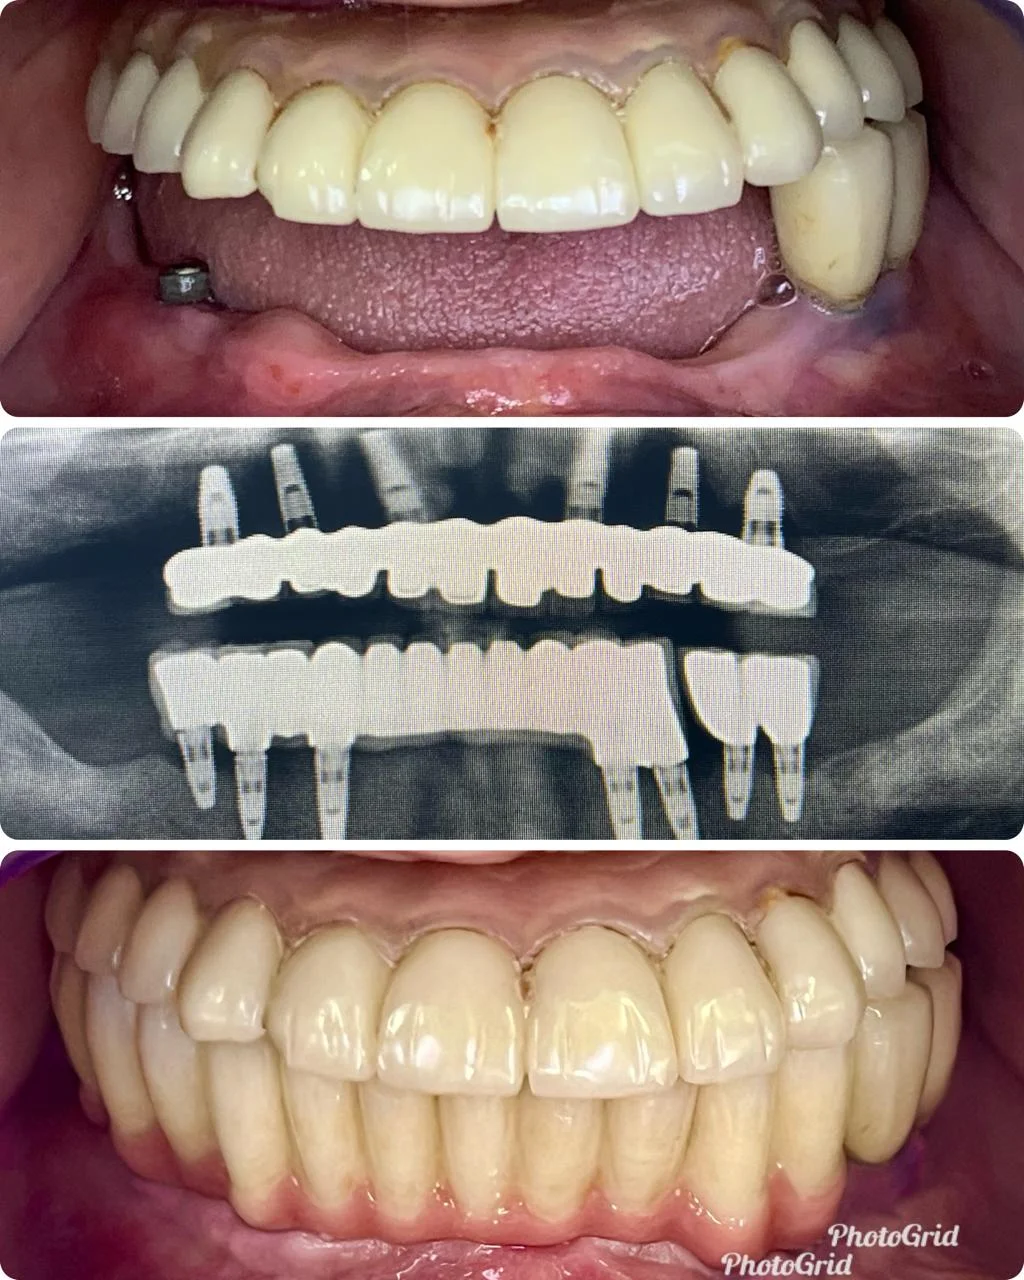

Showing Our Expertise In Dental Implantology

All-on-4 Implants (Per Jaw)

All-on-6 Implants (Per Jaw)